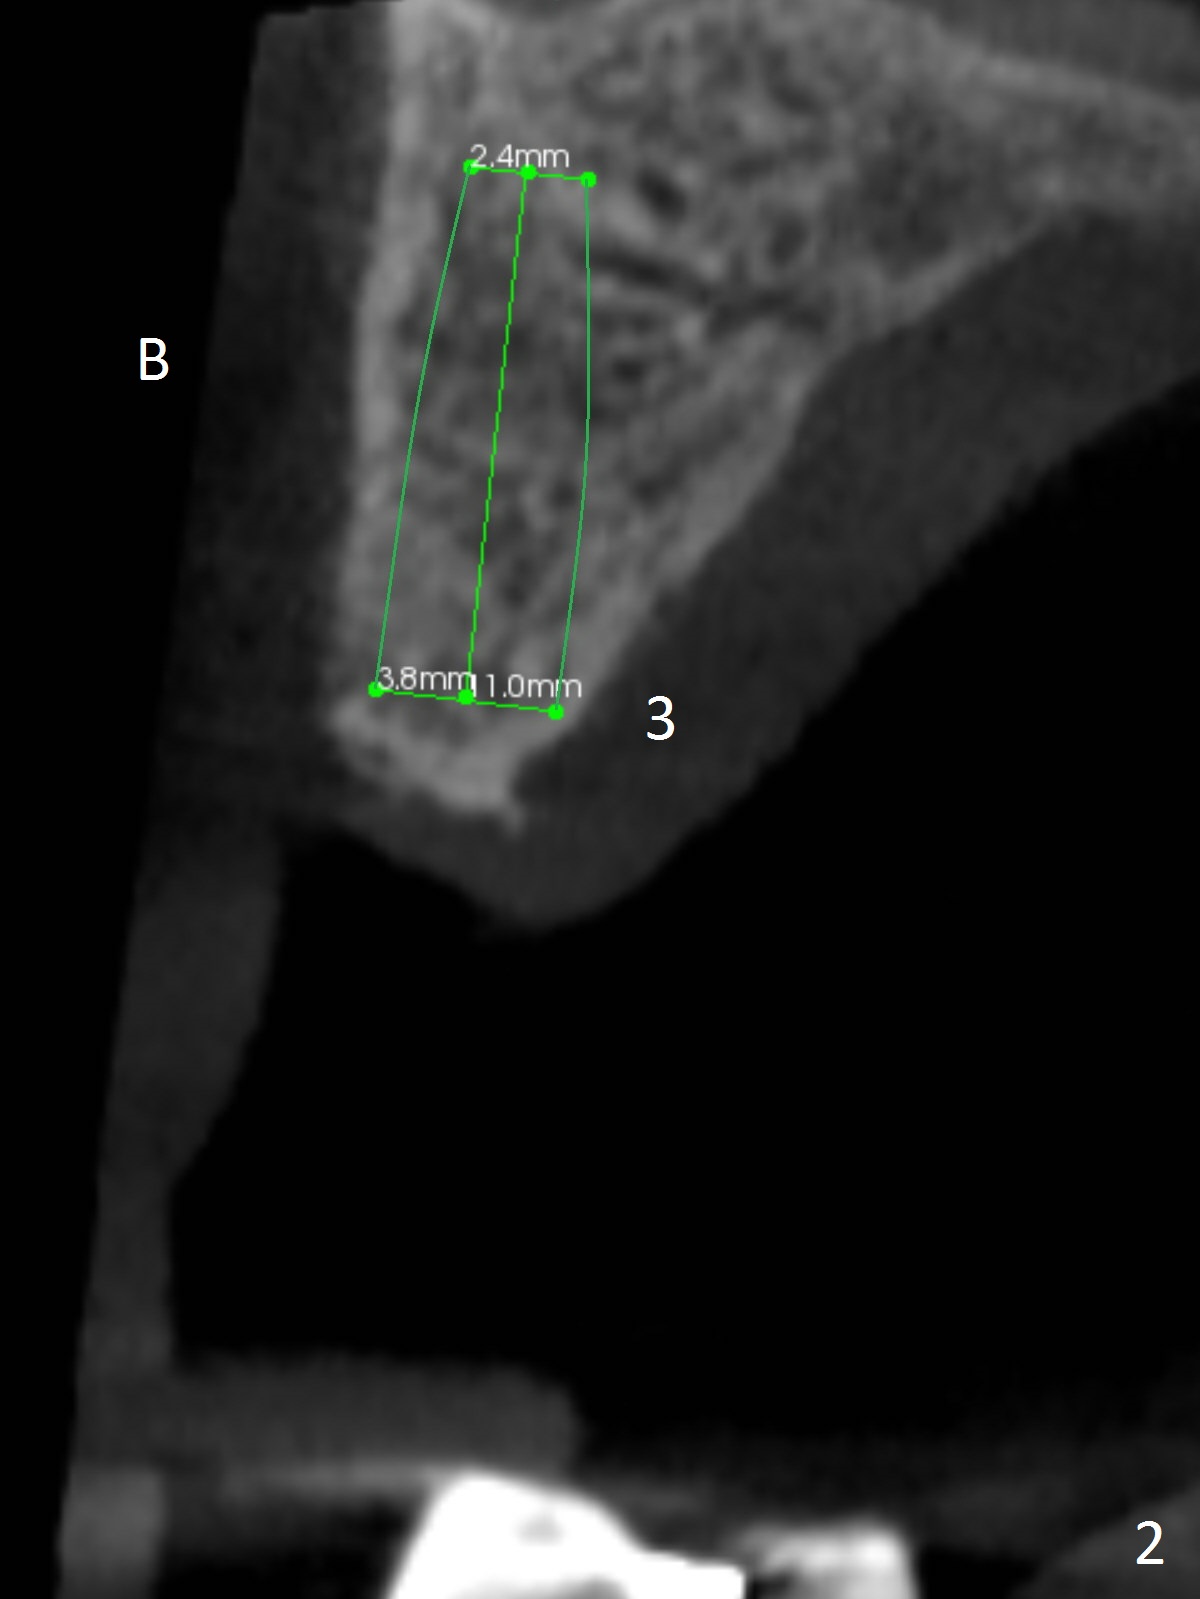

A 83-year-old woman requests lower RPD to replace #18-20 and 23-26 (Fig.1), although UR FPD supported by implants at #3 and 5 (Fig.2,3) is a better option. For the RPD, an implant will be placed at #18 (Fig.4) or 17 (Fig.5) with ball abutment. At #18, a shorter implant will be placed at the top of the Inferior Alveolar Canal (brown), while at #17, a longer implant will be placed buccal (B) to the canal.